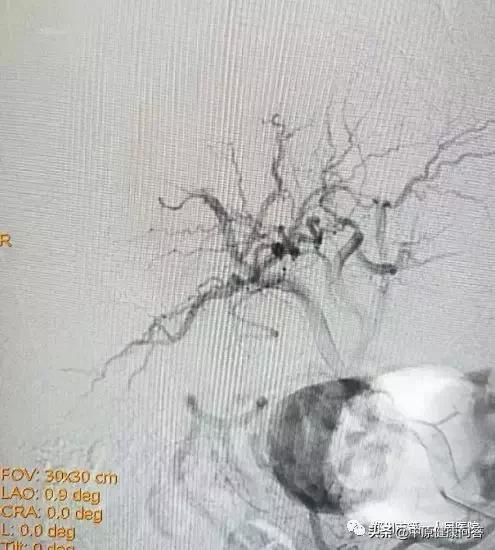

DSA造影术发现异常染色肿瘤血管,且造影剂外溢,证实肝癌破裂出血

次日早上,立即为康先生行肝动脉造影并栓塞术,术中见患者康先生肝右后动脉肿瘤染色明显且有造影剂外溢,结合该病史及CT考虑肝右后动脉破裂出血,给予栓塞治疗。